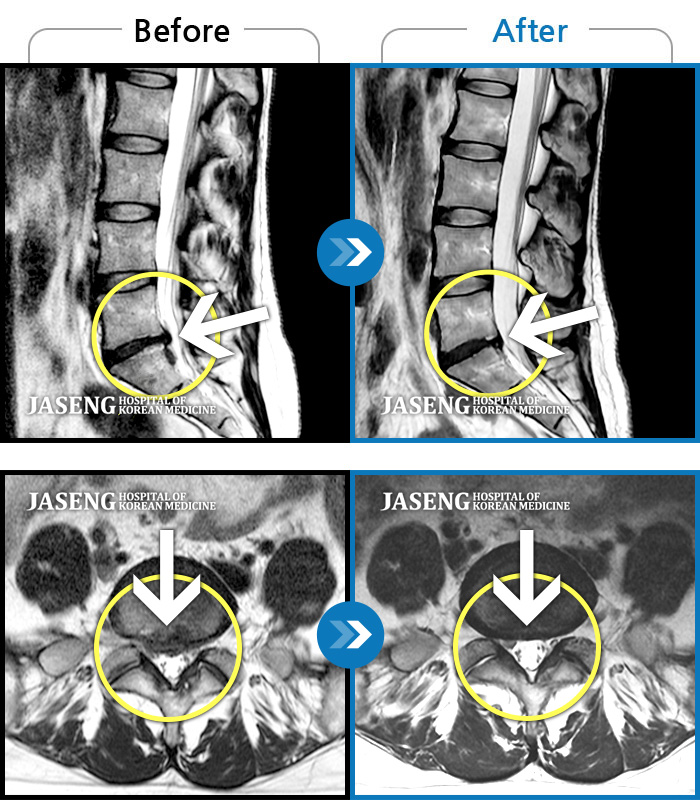

안녕하세요.방금 배아프다고 선생님찾아뵙고 진료받았죠 ㅎㅎ 후기를 이제서야 올리네요. 4년전인가 퇴행성디스크를 진단받고 양방병원 이곳저곳을 전전긍긍하며 속썩었던기억이나네요. 여러병원에서 수술을해야한다는 말에 젊은나이에 걱정을많이했었습나다. 심하게 아플때는 아침에 잠에서깨고 바로일어나지도못하고앉지도못해 회사생활이 힘들었는데 성생님만나뵙고 꾸준한치료 덕에 이렇게 허리가 안아프게되어 너무행복합니다. MRI는다른곳에서 찍어본거긴하지만 돌출된 디스크가 들어갔다는말에 신기했었습니다. 생활습관을바꾸고자 노력했고, 무엇 보다 선생님을 믿고 의지한 결과가아닐까 생각됩니다. 너무 감사드리고 MRI사진은 공유해드려야하는데 자꾸까먹네요 ㅎ